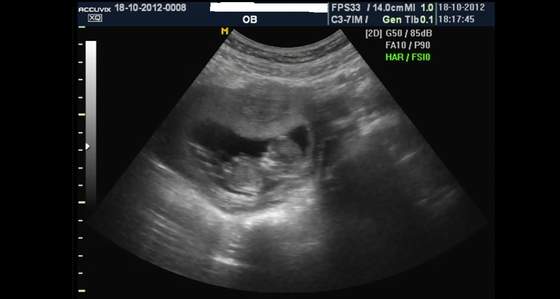

Ja już po wizycie, dzidzia rośnie jak powinna i jest wszystko w porządku. Ułożyła się tak, że doktórka nic nie dostrzegła czy coś tam dynda czy nie

Termin z USG to 1.05.2013 czyli ledwo się łapię na majóweczkę.

Dołączam zdjęcie mojego 4,5 cm szczęścia.

Maluszek jest piękny i całkowicie zdrowy